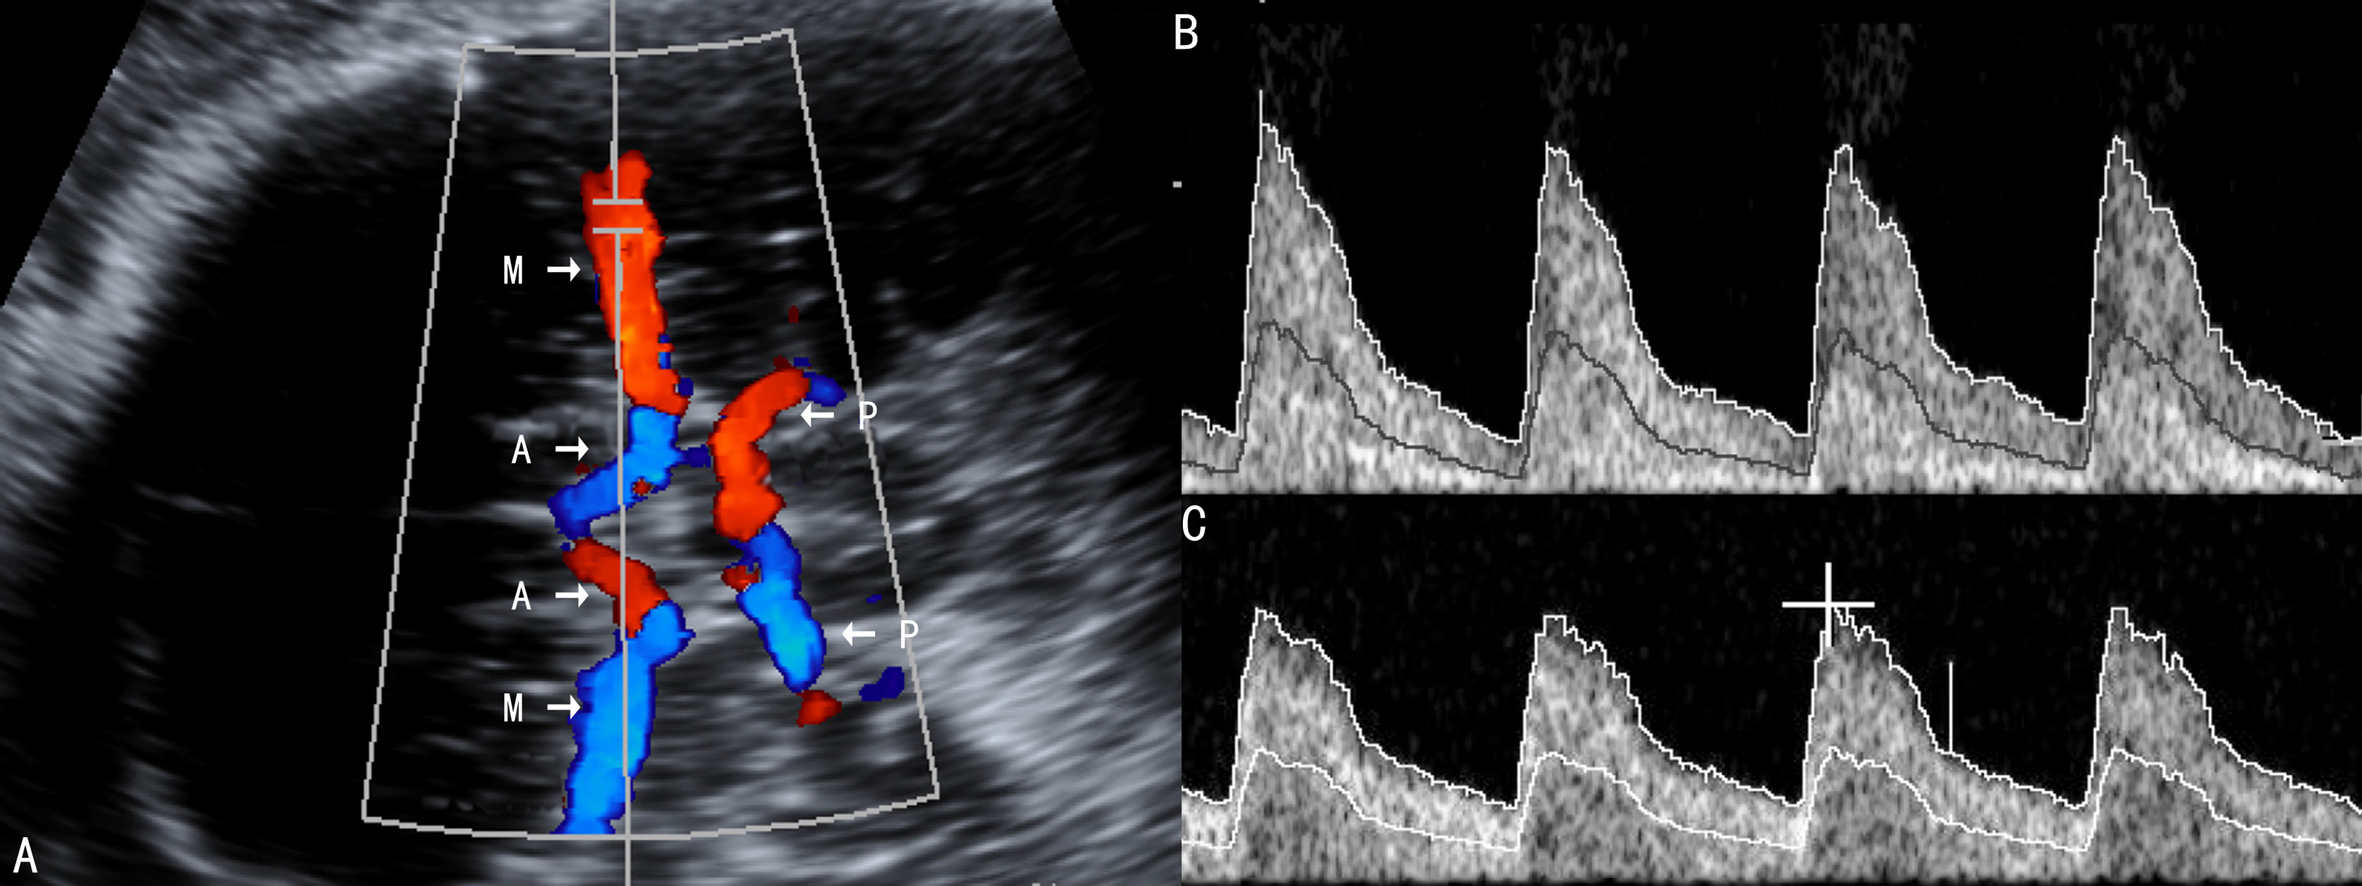

2. FMCA 在FUA血流变化的同时,由于“脑保护效应”,胎儿大脑、心脏和肾上腺的血流增加,多普勒超声检查可以显示FMCA血流速度S/D和阻力指数、搏动指数降低(图2),但胎儿缺氧达到一定的程度时,则可以引起S/D、阻力指数和搏动指数的增加、大脑的血流灌注量降低。因此,FMCA的多普勒超声检查与胎儿缺氧、FGR的严重程度并不完全一致,单独使用PIMCA检查时有很大的局限性,但一旦发现其异常,特异性可以达到90%。因此检查FMCA要注意胎儿缺氧的程度、FGR的进展,结合其他临床资料进行甄别、分辨。但也有研究者认为在晚期妊娠中FMCA的血流较FUA的改变更有意义。

图2 FGR时大脑中动脉血流速度曲线变化

A:正常大脑主动脉血流速度曲线 B:FCR时大脑中动脉舒张期血流增加